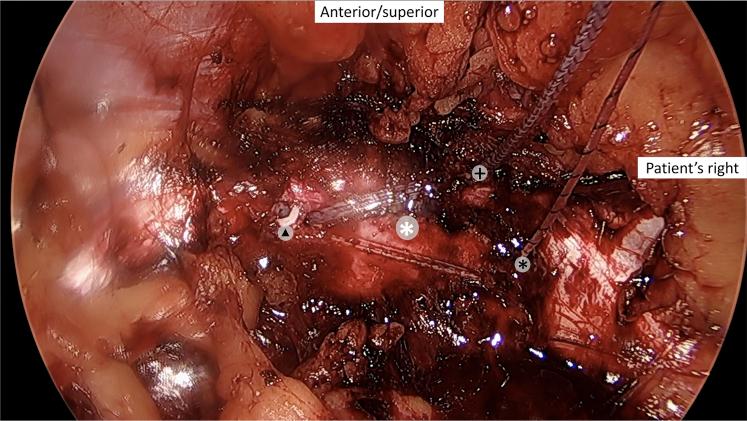

Laparoscopic Treatment of Pubic Symphysis Instability With Anchors and Tape Suture.

Patients with pubic symphysis instability who had failed nonoperative treatments may benefit from surgical repair. This disease process is rare, most commonly seen in postpartum women and athletes, and its surgical treatment is invasive and nonphysiological. Currently described surgical interventions, although limited, include plating, which provides an overly rigid construct with the risk of failure and possibly poor long-term outcomes particularly in athletes, and treatments such as curettage, more commonly used in the treatment of osteitis pubis. An emerging option is minimally invasive laparoscopic fixation using knotless anchors with a tape suture in a crisscross configuration. This possibly allows more physiological movement of the pubic symphysis in a less invasive manner. A detailed technical description and discussion of the technique are provided.

耻骨联合不稳定且非手术治疗失败的患者可能从手术修复中获益。这种疾病过程罕见,最常见于产后女性和运动员,其手术治疗具有侵入性且不符合生理状态。目前描述的手术干预措施虽然有限,但包括钢板固定,这会提供过于刚性的结构,存在失败风险,尤其在运动员中可能导致不良的长期预后,还有诸如刮除术等治疗方法,更常用于耻骨炎的治疗。一种新兴的选择是使用无结锚钉和带缝线以交叉配置进行微创腹腔镜固定。这可能以微创方式使耻骨联合实现更多的生理性活动。本文提供了该技术的详细技术描述和讨论。